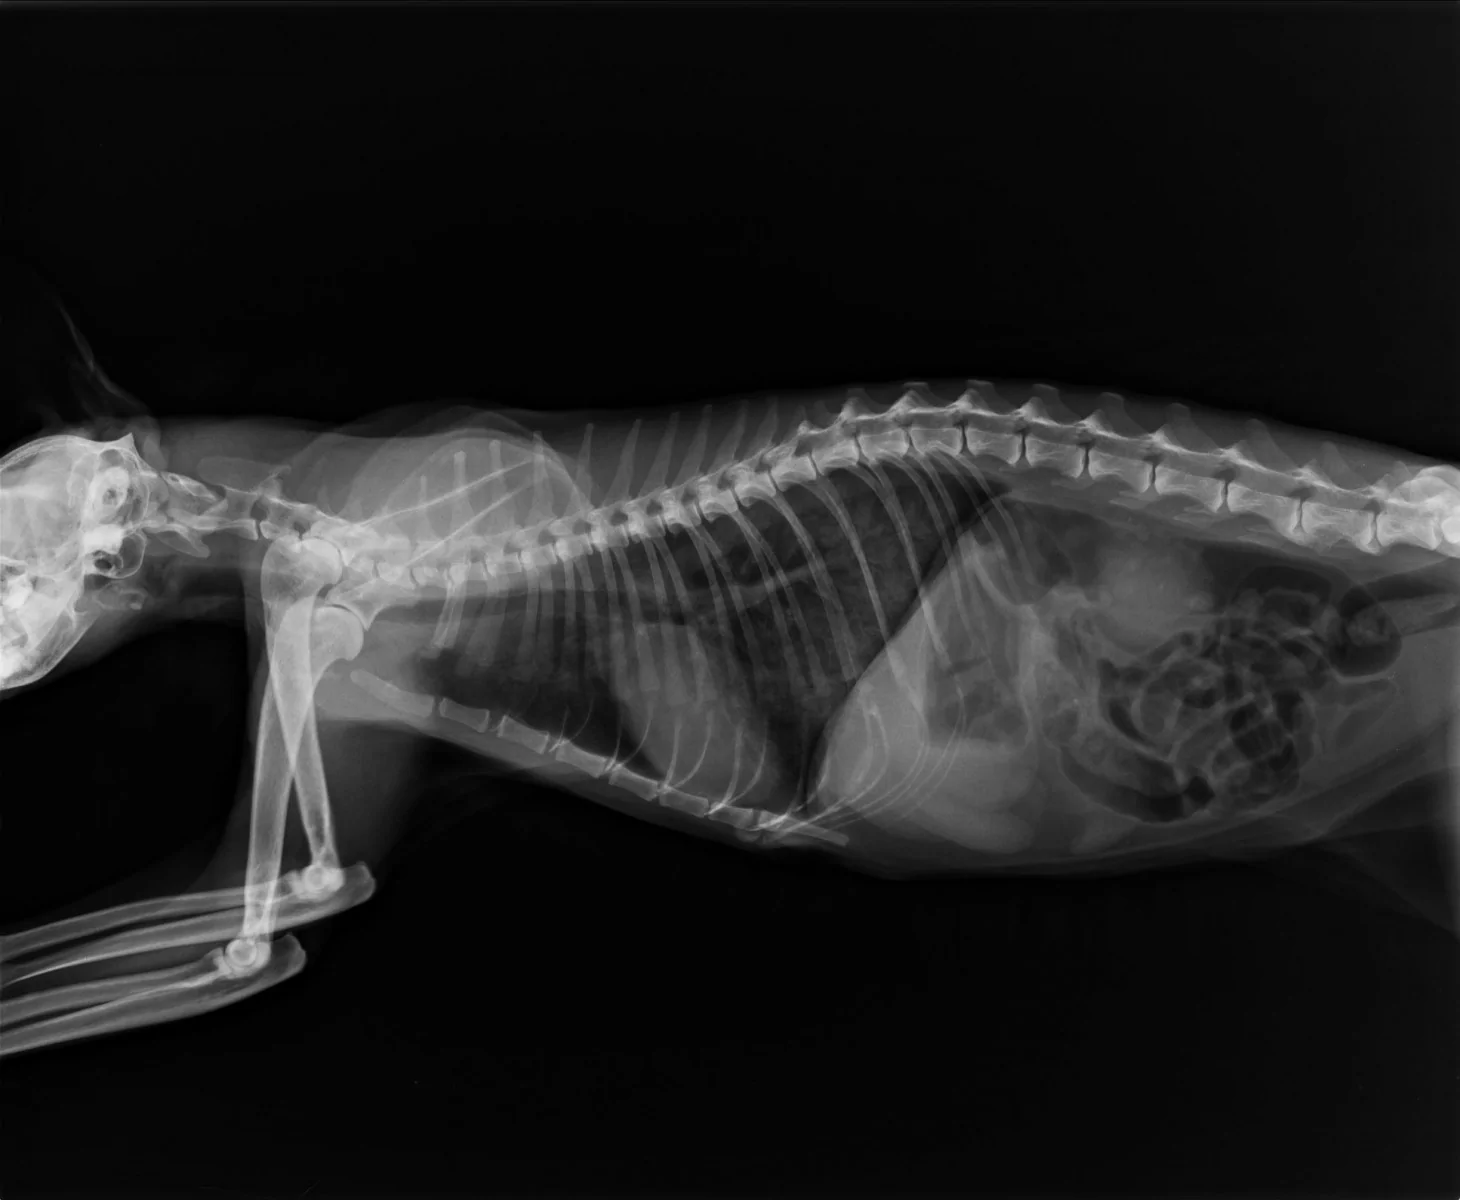

Рентген как метод диагностики легочных гельминтов у кошек: что нужно знать владельцам

Легочные гельминты у кошек – это опасные паразиты, которые могут вызвать серьезные заболевания дыхательной системы. Одним из эффективных методов диагностики является рентгеновское исследование, позволяющее выявить их наличие в легких. В этой статье мы расскажем, как этот метод помогает в диагностике и что нужно знать владельцам домашних питомцев.

Рентген может помочь не только обнаружить гельминтов, но и выявить возможные осложнения в легких.

Рентгеновское исследование помогает выявить даже скрытые инфекции, которые могут не проявляться на начальных стадиях.